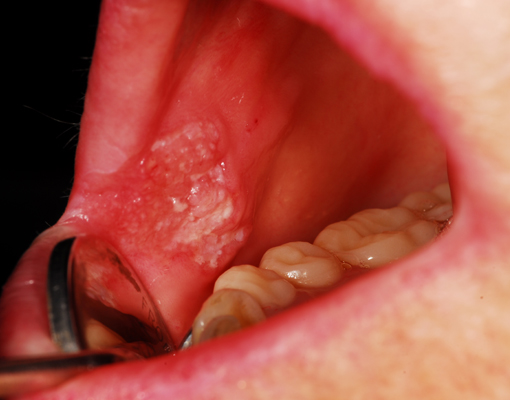

Biopsy is a procedure which involves the removal of a piece of tissue from the oral cavity, so that it can be analyzed in a laboratory. If there are certain signs and symptoms such as white or red area in the mouth, non healing ulcer or if your doctor has identified an area of concern, you may have to undergo a biopsy establishment of proper diagnosis, which will help in providing appropriate treatment.

Types of biopsy procedures used to diagnose precancer, cancer or any other lesion:

Incisional biopsy: When the lesion is large, then a small piece of tissue is removed from the entire lesion.

Excisional Biopsies : When the lesion is small and if it appears to be benign or not cancerous, then it will be removed in total.